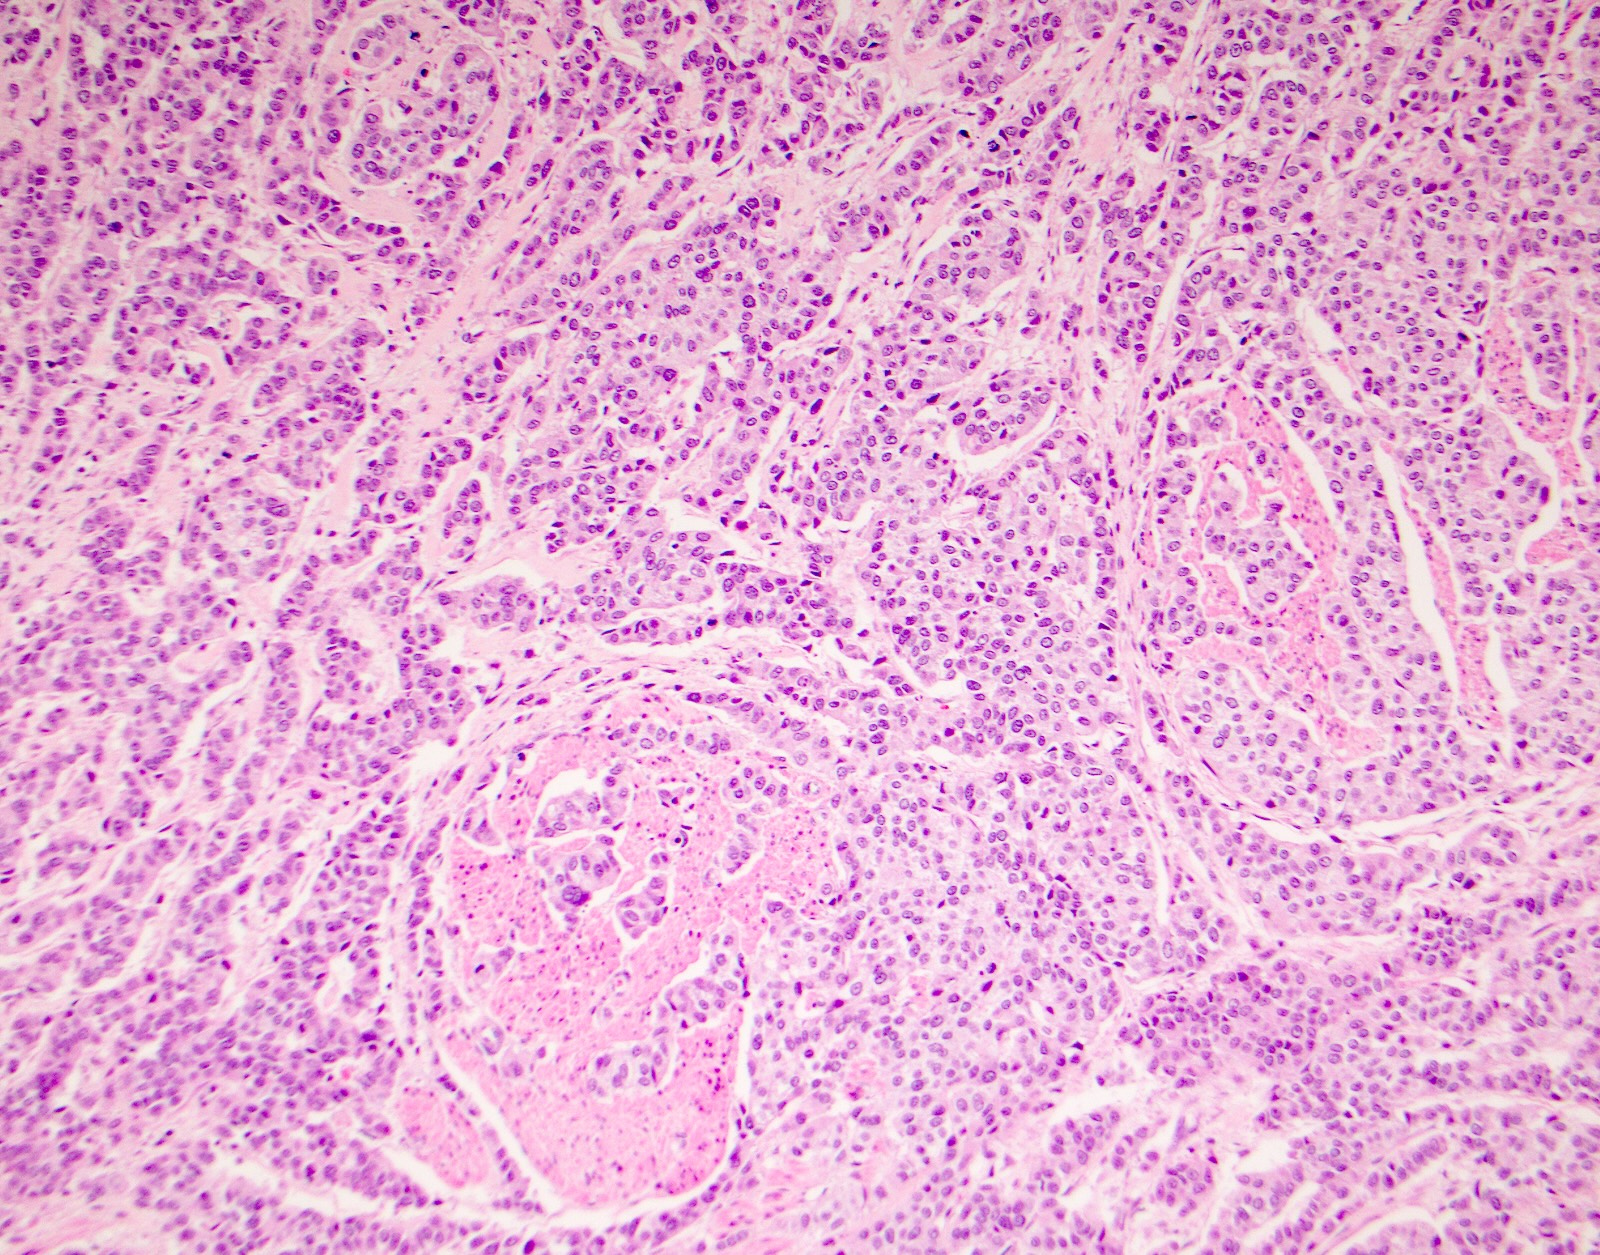

Microscopic (histologic) images

Contributed by Surekha Bantumilli, M.D. and Dimitri G. Trembath, M.D., Ph.D.

Practice question #1

A 65 year old man presents with elevated prostate specific antigen (PSA) and undergoes a prostate biopsy, stained with high molecular weight cytokeratin (HMWCK) (shown above). What is the most likely interpretation of this staining pattern?

Practice answer #1

A. Benign prostate tissue. The basal layer of benign prostate glands will stain with high molecular weight cytokeratin. Answer D is incorrect because staining will be lost on prostatic adenocarcinoma. Answer C is incorrect because high molecular weight cytokeratin staining can be present in high grade prostatic intraepithelial neoplasia but is not diagnostic by itself for this entity. Answers B and E are incorrect because the glandular appearance outlined by the high molecular weight cytokeratin staining is not consistent with either seminal vesicle or urothelial carcinoma.